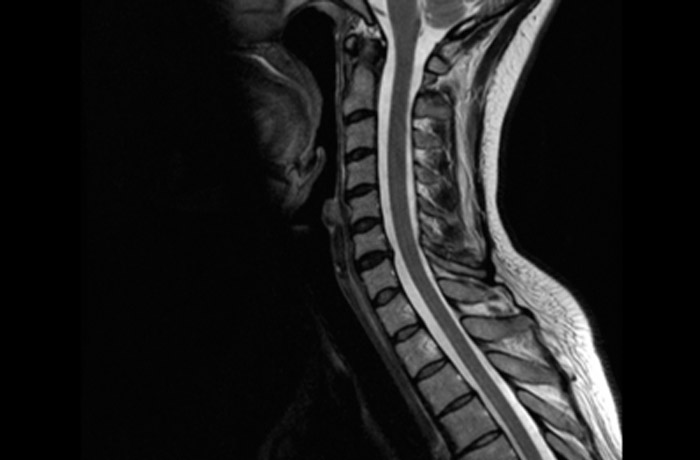

МРТ шейного отдела позвоночника

МРТ шейного отдела позвоночника – высокоинформативный и современный метод диагностики, который позволяет выявить различные патологии мягких тканей, сосудов, позвонков, межпозвонковых дисков.